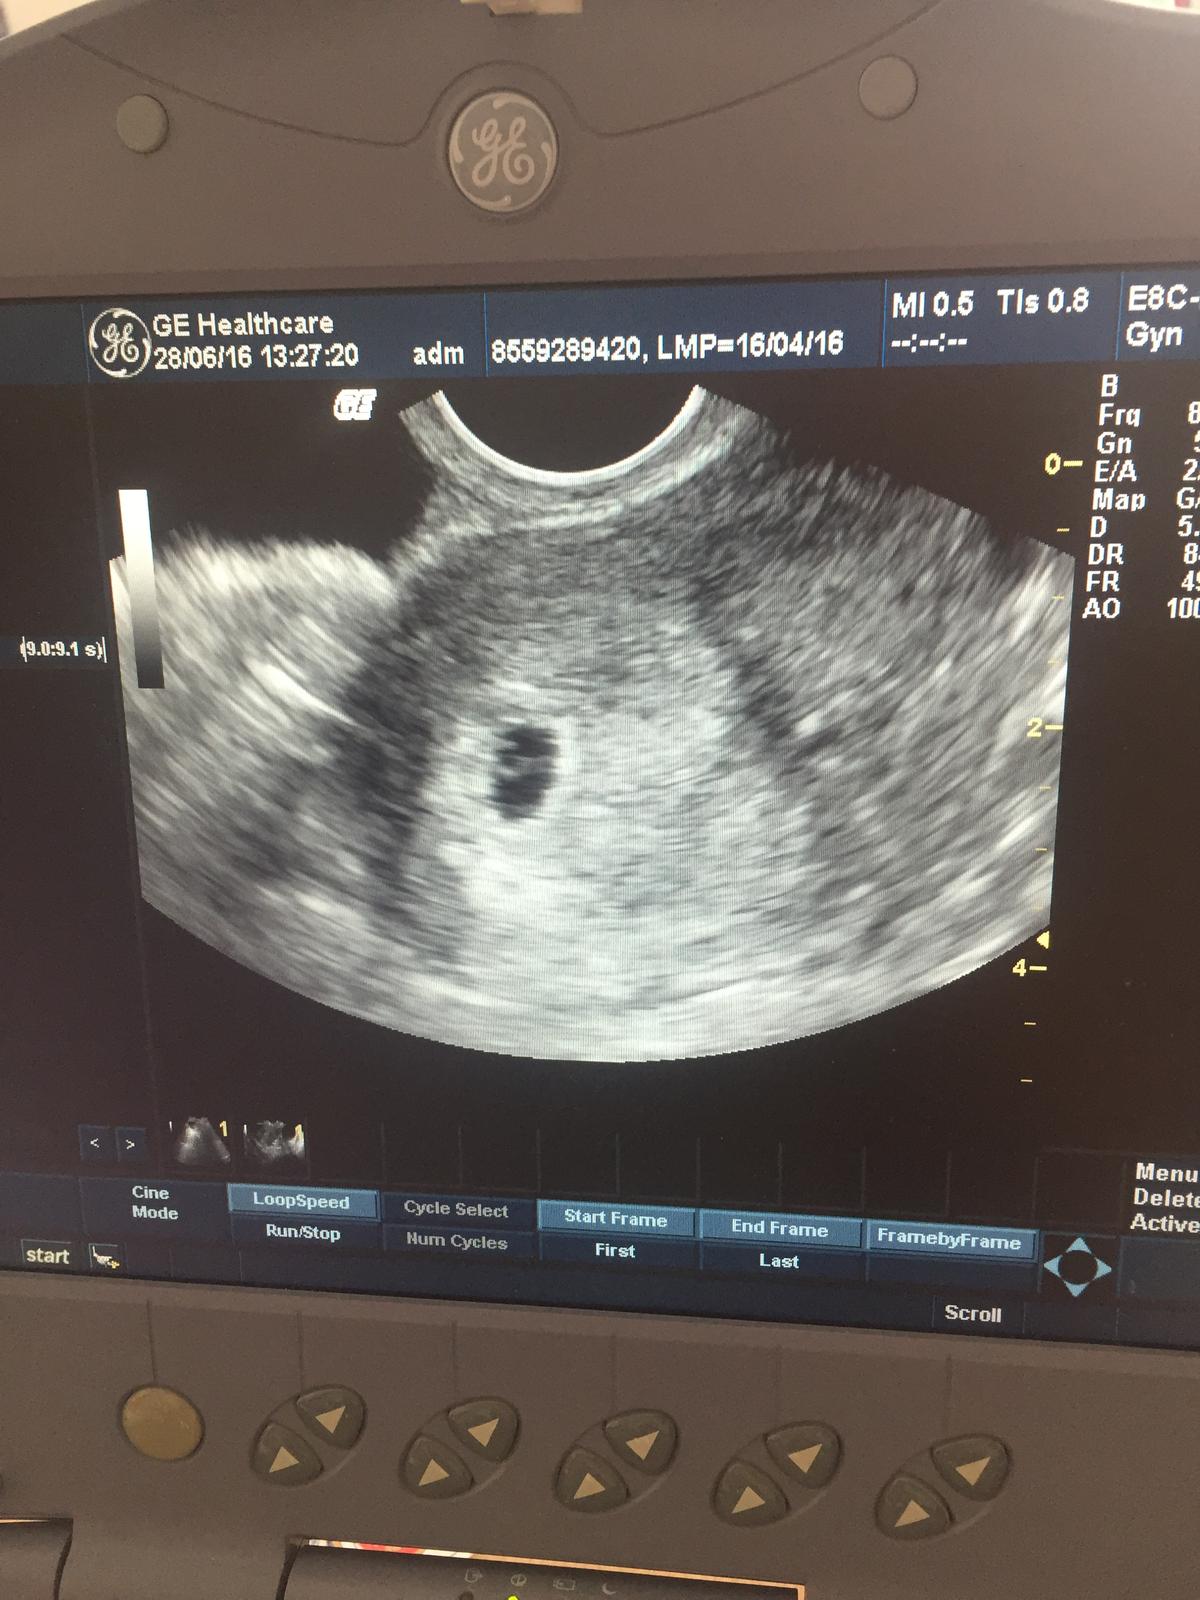

@butterfly333 zlty vačok alebo žlte teliesko je zaciatok vyvoja babatka 🙂 dakujeeem :-*